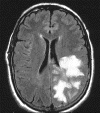

The patient became more confused and incoherent. A CT scan showed a mass lesion with edema on the left side of the brain that was suggestive of a tumor. MRI showed a large infiltrating lesion involving the left parietal lobe, occipital lobe, a portion of the parietal lobe, and part of the basal ganglia. The lesion was mildly enhancing after gadolinium injection. A stereotactic biopsy was performed. Representative MRI images and histologic images are illustrated below.

MR Imaging of the case:

The FLAIR sequences (Panel A) demonstrate an extensive abnormality with increased intensity signal and irregular borders that involves the left occipital, parietal and dorsal frontal lobes. Although the lesion is quite extensive the mass effect is minimal. On the post contrast T1-weighted sequences (Panel B) there is enhancement only in the anterior border of the lesion. The limited mass effect along with the “crescent” rim enhancement are suggestive of  demyelinating process, likely tumefactive multiple sclerosis.